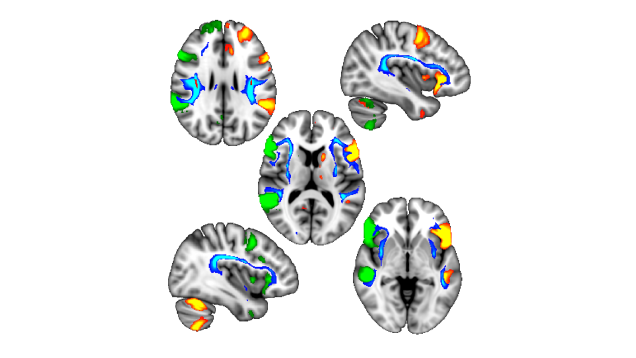

A series of genetic variants can influence handedness, according to a new paper.